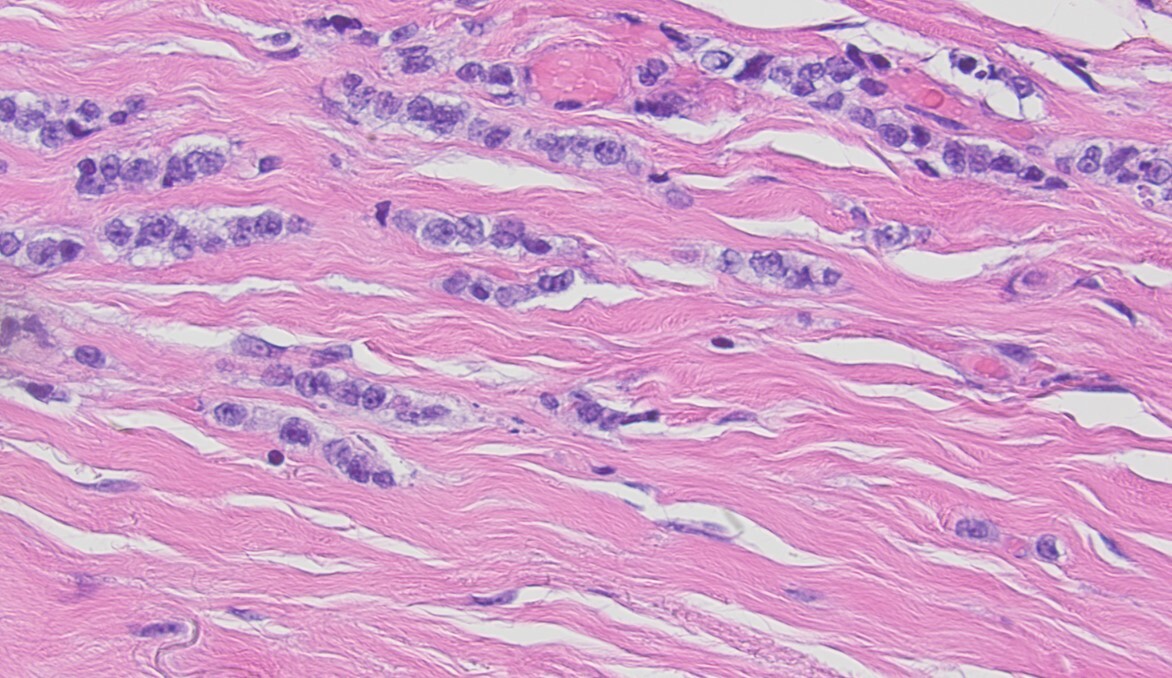

Invasive lobular carcinoma (ILC) is the most common special subtype of breast carcinoma. In contrast to carcinoma of no special type (NST, also known as invasive ductal carcinoma or IDC), ILC lacks duct formation and characteristically shows single cell infiltrative growth pattern which is the results of biallelic inactivation of the CDH1 gene (codes for E-cadherin). ILC has been reported to show some unique clinical features compared to IDC. ILC forms a poorly defined mass and the tumor size is often underestimated on clinical exam and imaging. It is questionable whether the prognosis of ILC is better, similar, or worse than grade and stage-matched IDC. However, the pattern of metastasis is unique to ILC with more frequent metastasis to visceral organs such as gastrointestinal tract, uterus, and ovaries. ILC shows minimal response to neoadjuvant chemotherapy compared to IDC, but this relative resistance to cytotoxic chemotherapy is likely due to receptor profile and proliferation (high receptor expression levels and lower proliferation in ILC) rather than due to the histological pattern itself.

To improve standardization of ILC diagnosis, we have been routinely performing E-cadherin to confirm first time ILC diagnosis at our institution since 2004-2005. However, in doing so routinely, we have encountered tumors that morphologically resemble ILC on hematoxylin and eosin (H&E) stain slides but demonstrate circumferential membranous reactivity for E-cadherin. We have always wondered if these tumors follow a clinical course similar to ILC or IDC and whether they demonstrate characteristic CDH1 mutations. We labeled these tumors lobular-like invasive mammary carcinoma (LLIMCa or LiMCa) for our study and compared and contrasted their clinical-pathologic features with grade matched IDC and ILC. We also performed an exploratory molecular analysis of 7 LiMCa and 7 ILC to understand the molecular mechanisms that results in this morpho-immunohistologic appearance.

In summary, we describe the clinical-pathological features of LiMCa – a low to intermediate grade mammary carcinoma that shows single cell infiltrating growth pattern (like classical-type lobular carcinoma) but shows retained membranous expression of E-cadherin and other related proteins (p120 and beta-catenin). These tumors lack the characteristic CDH1 mutations but a proportion of them show CDH1 promoter methylation. Their clinical-pathological features are intermediate between ILC and IDC. The prognosis is related to tumor stage and multivariable prognostic model of Magee Equation score.3 Using LiMCa terminology will help us learn more about these peculiar tumors.